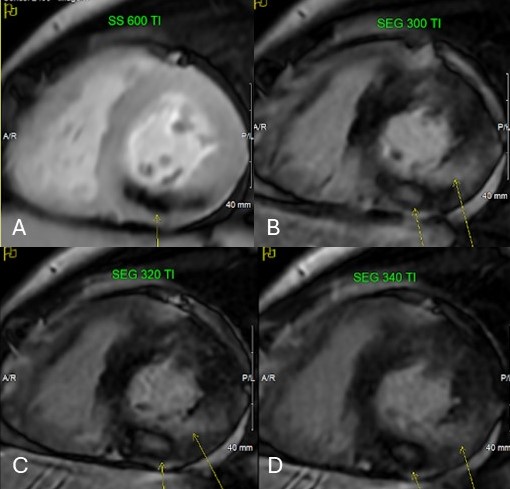

Figure 3: A. Inversion recovery image at higher inversion time of 600 msec showing area of microvascular obstruction (arrow) within the myocardial wall. Same area at usual inversion time of 300 msec (B), 320 msec (C) and 340 msec (D) (small arrow) showing well demarcated region of hyperintensity suggesting no contrast uptake. The long arrows indicate subendocardial to near transmural late gadolinium enhancement.